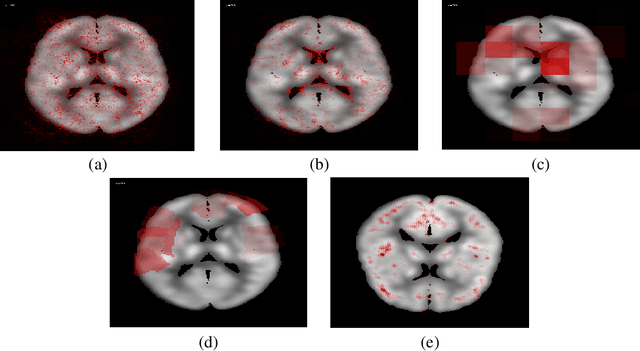

Abstract:In recent days, Convolutional Neural Networks (CNN) have demonstrated impressive performance in medical image analysis. However, there is a lack of clear understanding of why and how the Convolutional Neural Network performs so well for image analysis task. How CNN analyzes an image and discriminates among samples of different classes are usually considered as non-transparent. As a result, it becomes difficult to apply CNN based approaches in clinical procedures and automated disease diagnosis systems. In this paper, we consider this issue and work on visualizing and understanding the decision of Convolutional Neural Network for Alzheimer's Disease (AD) Diagnosis. We develop a 3D deep convolutional neural network for AD diagnosis using brain PET scans and propose using five visualizations techniques - Sensitivity Analysis (Backpropagation), Guided Backpropagation, Occlusion, Brain Area Occlusion, and Layer-wise Relevance Propagation (LRP) to understand the decision of the CNN by highlighting the relevant areas in the PET data.